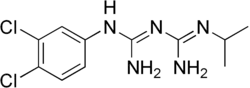

Chlorproguanil

| IUPAC name

1-[Amino-(3,4-dichloroanilino)methylidene]-2-propan-2-ylguanidine

| C11H15Cl2N5 | |

| Molar mass | 288.18 g/mol |